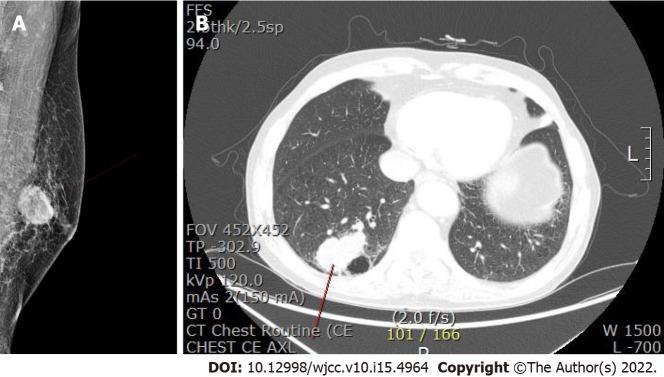

We report a case of MBC in a 78-year-old man. He visited our clinic with a palpable mass on the left breast with no masses in the axillary areas. He had previously undergone robot-assisted laparoscopic radical prostatectomy for prostate cancer, but there was no family history of malignancy. The breast mass was visible on ultrasonography, mammography, and magnetic resonance imaging, and chest computed tomography revealed a lung mass in the posterior basal segment of the right lower lobe. The patient was diagnosed with metaplastic carcinoma on core needle biopsy with lung metastasis. Total mastectomy with sentinel lymph node biopsy and video-assisted segmentectomy of the right lung was performed. However, multiple metastases appeared 3 mo after surgery in the brain, chest, and abdomen, and the patient died 5 mo after the initial diagnosis.

我们报告一例78岁男性的MBC病例。他因左侧乳房可触及肿块前来我院就诊,腋窝区域未触及肿块。他曾因前列腺癌接受机器人辅助腹腔镜根治性前列腺切除术,但无恶性肿瘤家族史。乳房肿块在超声、乳腺X线摄影和磁共振成像中均可见,胸部计算机断层扫描显示右下叶后基底段有一个肺部肿块。经粗针活检确诊为化生性癌伴肺转移。行全乳切除术加前哨淋巴结活检及右肺电视辅助节段切除术。然而,术后3个月脑、胸、腹出现多处转移,患者在初诊后5个月死亡。